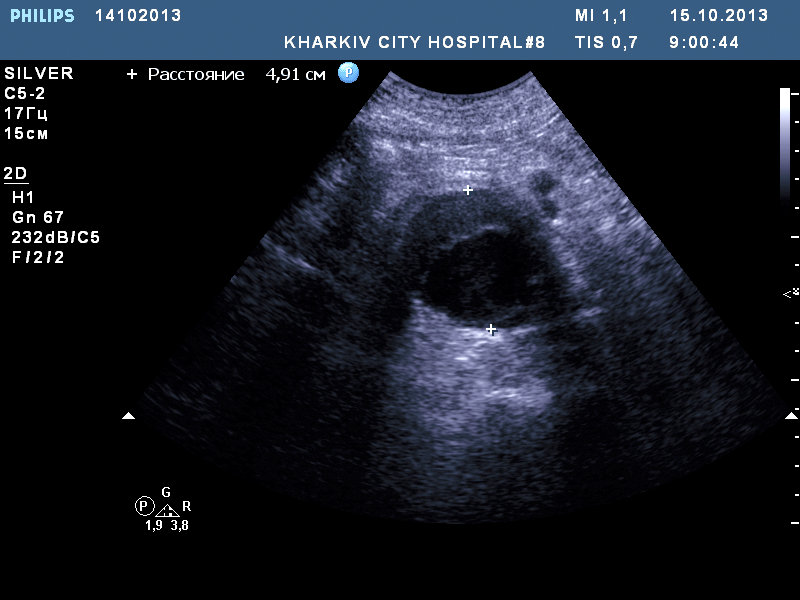

фиксированный тромб (размерами до 4.0смх 2.5см) в ушке левого предсердия (10.0см в поперечном размере) , состояние после пластики митрального клапана, склеротические изменения аорты с расширением восходящего отдела, кальциноз створок АК — незначительный АС, незначительная НАК, умеренная МН, дилатация левых полостей, правого предсердия, гипертрофия левого желудочка.

Также у данного пациента в брюшном отделе аорты имеется аневризма.